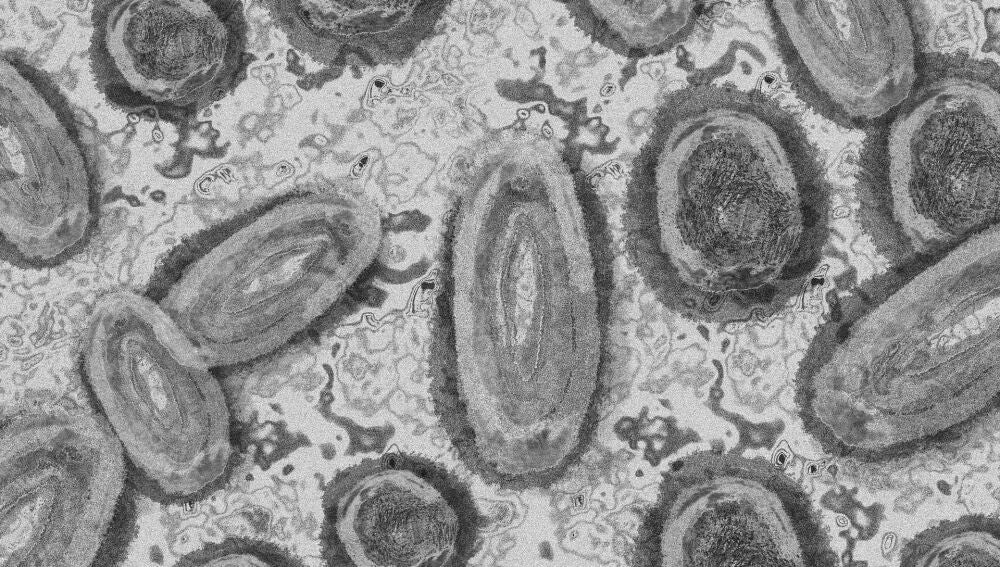

Las autoridades sanitarias creen que la viruela del mono se introdujo en Europa "recientemente"

El Centro Europeo para la Prevención y el Control de las Enfermedades descarta que el brote más grande hasta la fecha lleve en España tres años.

Viruela del monoPixabay